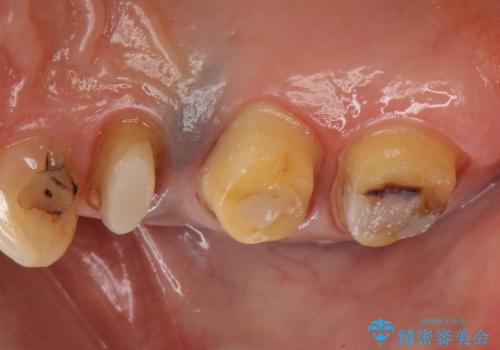

診査の結果痛みの原因は右上7番目だったため、古い樹脂と虫歯を除去後、オールセラミッククラウンによる補綴を行いました。

また右上5、6番目の歯も治療を希望されたため、オールセラミッククラウンによる補綴を行いました。

今回用いたオールセラミッククラウンはジルコニアフレームという白い素材の上にセラミックを盛っているため、審美性が非常に高いのが特徴です。

また、ジルコニアは人工ダイヤモンドの材料にも使われているほど高い強度を持っており、そのためオールセラミッククラウンは審美性だけでなく、奥歯やブリッジの補綴も可能とするクラウンです。